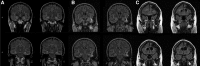

Post-traumatic epilepsy (PTE) is a consequence of traumatic brain injury (TBI), occurring in 10-25% of patients with moderate to severe injuries. The development of animal models for testing antiepileptogenic therapies and validation of biomarkers to follow epileptogenesis in humans necessitates sophisticated understanding of the subtypes of PTE, which is the objective of this study. In this study, retrospective review was performed of patients with moderate to severe TBI with subsequent development of medically refractory epilepsy referred for video-electroencephalography (EEG) monitoring at a single center over a 10-year period. Information regarding details of injury, neuroimaging studies, seizures, video-EEG, and surgery outcomes were collected and analyzed VSports手机版. There were 123 patients with PTE identified, representing 4. 3% of all patients evaluated in the epilepsy monitoring unit. Most of them had localization-related epilepsy, of which 57% had temporal lobe epilepsy (TLE), 35% had frontal lobe epilepsy (FLE), and 3% each had parietal and occipital lobe epilepsy. Of patients with TLE, 44% had mesial temporal sclerosis (MTS), 26% had temporal neocortical lesions, and 30% were nonlesional. There was no difference in age at injury between the different PTE subtypes. Twenty-two patients, 13 of whom had MTS, proceeded to surgical resection. At a mean follow-up of 2. 5 years, Engel Class I outcomes were seen in 69% of those with TLE and 33% of those with FLE. Our findings suggest PTE is a heterogeneous condition, and careful evaluation with video-EEG monitoring and high resolution MRI can identify distinct syndromes. These results have implications for the design of clinical trials of antiepileptogenic therapies for PTE. .